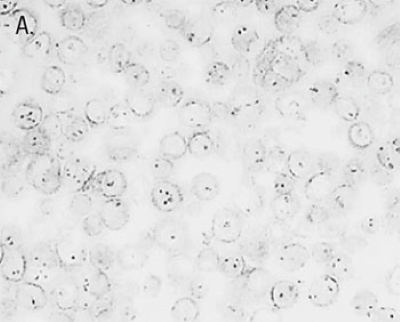

◆AMPIVIEW™ RNA探针可以用正义探针检测DNA拷贝,用反义探针检测DNA和RNA

|

|

检测SiHa细胞中的HPV 16/18(1-3个HPV整合拷贝),A. 用AMPIVIEW™ HPV 16/18正义RNA探针仅检测病毒DNA,B. AMPIVIEW™ HPV 16/18反义RNA探针同时检测细胞中的病毒DNA和病毒RNA。